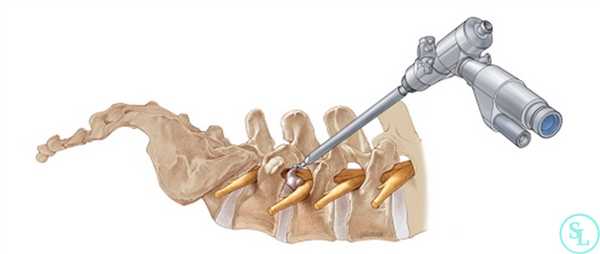

Как проходит операция по эндоскопическому удалению грыжи шейного отдела

Нейрохирург делает небольшой (7 мм) надрез на задней поверхности шеи. Под контролем рентгена в рану устанавливается рабочий порт, в который вводится эндоскоп диаметром 6 мм, оснащенный микрощипцами, микрокамерой, световым и промывным каналами. Грыжа удаляется под детализированным визуальным контролем. В ходе вмешательства нейрохирург аккуратно раздвигает прилегающие мышцы, связки и волокна мягких тканей, не травмируя их. Чтобы получить доступ в позвоночный канал и провести декомпрессию спинномозгового корешка, выполняется небольшая фораминотомия (расширение межпозвонкового отверстия). После эндоскопического удаления грыжи шейного отдела, то есть очищения позвоночного канала, боль проходит сразу. Нейрохирург наносит единственный шов, который снимается через 10 дней. Подвижность возвращается в тот же день. Срок госпитализации — 1 сутки, после чего врач выписывает пациента из клиники домой с несложными рекомендациями по восстановлению. Восстановление проходит комфортно, поэтому в течение месяца пациент может вернуться к работе и привычной жизни.

Эндоскопический вид

Эндоскопическая операция в нейрохирургии позвоночника применяется сравнительно недавно, за рубежом ее начали внедрять в средине 90-х, в России только спустя 10 лет. Эндоскопия по поводу декомпрессии - это самая миниинвазивная методика резекции патологических тканей через незначительный разрез (1-1,5 см) с использованием телескопического зонда и комплекта инструментов, которые вводятся в его рабочую полость. Сеанс длится в среднем 45 минут. На реабилитацию уходит примерно 60 суток.

Методика, когда хирург производит резекционные мероприятия через тонкую эндоскопическую трубку диаметром всего в 6-8 мм, является наиболее корректной по отношению к здоровым кожным и окружающим мышечно-связочным структурам. Благодаря этому пациент легче и быстрее переносит восстановительные этапы.

Эндоскопия предельно минимизирует риски интра- и послеоперационных осложнений за счет высочайших возможностей увеличения операционного поля с четкой передачей его изображения на хирургический монитор в реальном времени. Оперативное вмешательство с эндоскопом также располагает уникальными способами доступа: